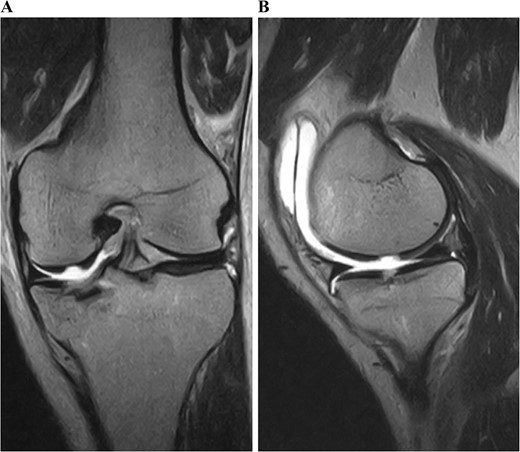

A 49-year-old male patient fell while playing soccer and visited our hospital with severe pain and swelling in his left knee. A lateral-view plain radiograph showed articular depression of the tibial plateau (Fig. 1). Three-dimensional reconstructed computed tomography (CT) scan revealed a 5-mm depression of the medial articular surface and a split in the medial plateau (Fig. 2). The fracture was classified as AO/OTA 41B3.2 and Schatzker type 2 [6, 7]. MRI scan showed a medial femoral cartilage injury that appeared as a kissing lesion opposite the tibial fracture. The length and width of the cartilage defect on the femoral condyle were 18 mm and 20 mm, respectively (Fig. 3). A part of the peripheral cartilage around the defect was suspected to be delaminated, and the defect was estimated to exceed 4 cm2.

Preoperative T2-weighted magnetic resonance images of the left knee. A cartilage injury of the medial femoral condyle appeared as a kissing lesion opposite the tibial plateau fracture. The coronal image revealed a 20-mm-wide cartilage injury (A). The sagittal image showed an 18-mm-long cartilage injury (B).